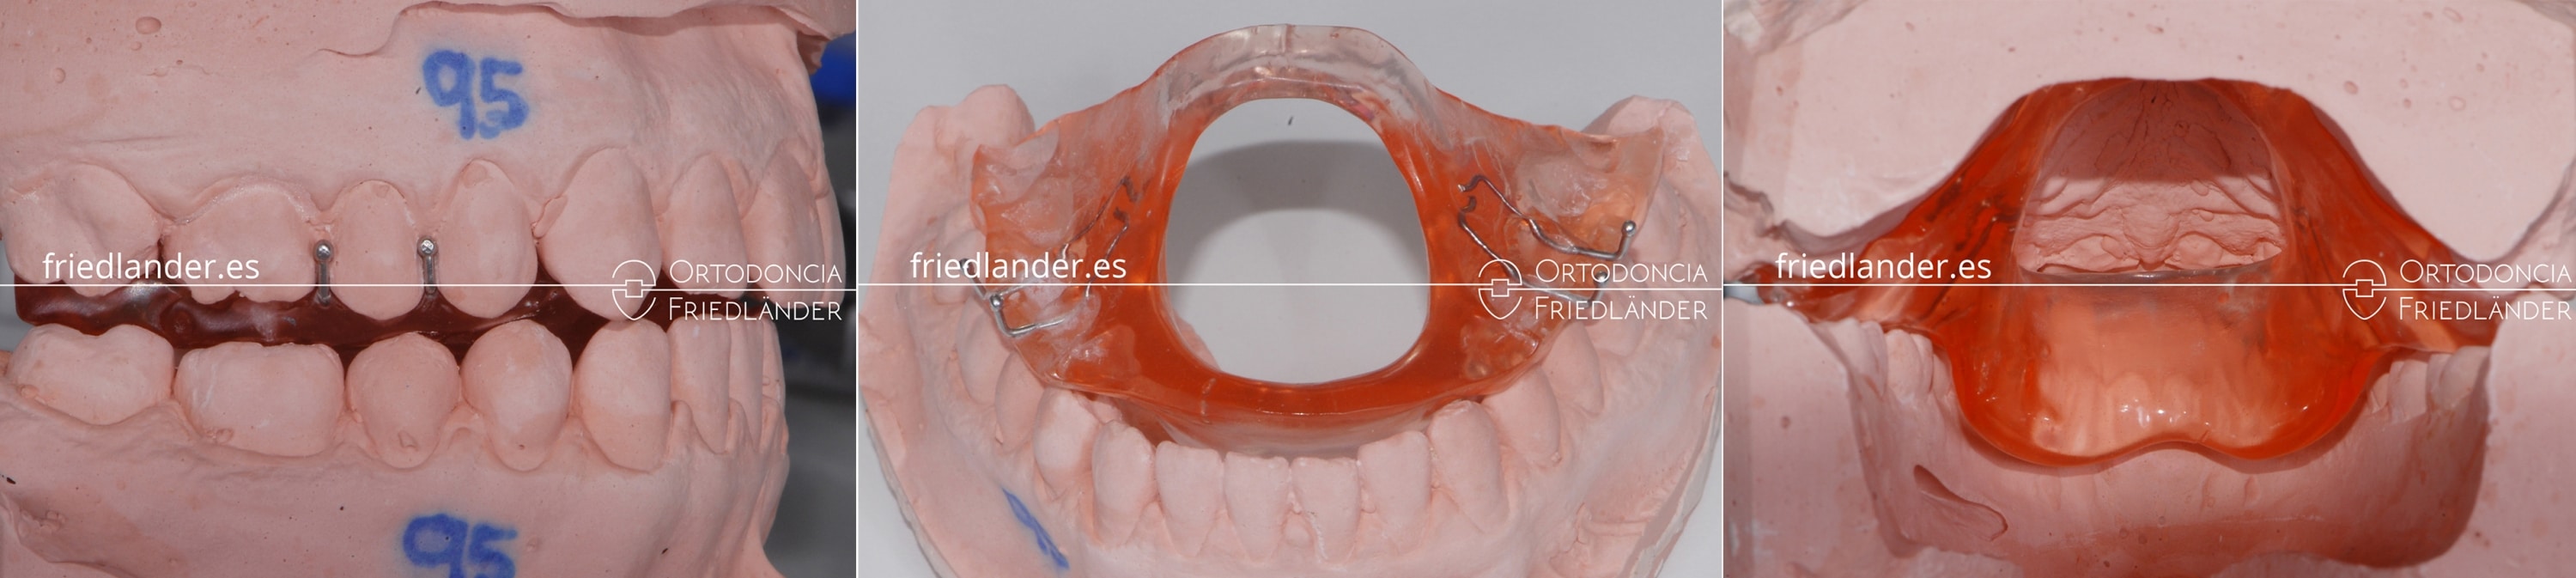

La última fase de cada tratamiento de ortodoncia es la fase de retención. Cada caso requiere retención para que no hayan recaídas después del tratamiento. En las mordidas abierta es aun más necesarios y el protocolo es aun más estricto. Para la retención de casos de mordida abierta uso siempre una retención fija superior e inferior y además como refuerzo un aparato que se llama envelope de Bonnet con bloques de mordida posteriores. (se puede abrir la imagen del aparato haciendo clic en la imagen)

Envelope de Bonnet colocado en los modelos de trabajo, se puede observar que la lengua no puede tocar los dientes anteriores mientras el aparato este colocado.

El envelope lingual de Bonnet fue ideado como un «envoltorio» para la lengua, para su reeducación y la corrección de la deglución. El envelope impide que la lengua pueda tocar los dientes anteriores. Hemos modificado el envelope original añadiendo unos bloques de mordida para ayudar a mantener el movimiento de intrusión conseguido. Para resumir, este aparato modificado tiene doble función; evita que la lengua empuje los dientes y mantiene la intrusión molar conseguida con los microtornillos. Este aparato es muy comodo de llevar (requiere un pequeño periodo de adaptación) y se lleva solo para dormir, momento que la lengua ejerce mucha presión sobre los dientes anteriores de manera inconsciente.